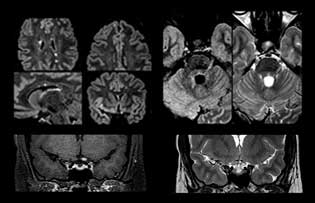

When multiple sclerosis (MS) is suspected, clinicians need a diagnosis early on, so treatment can begin as soon as possible. “A challenge for imaging is that MS lesions in the brain and spine may be very small,” says Dr. Savatovsky. “We need precise imaging to tell exactly where the lesion is, so we need high quality, very high resolution images, preferably in 3D[1]. We need to know if a high T2 signal intensity is suggestive of MS or just aspecific. And we want to visualize active lesions very well.”

“Ingenia 3.0T provides us very good image quality with high SNR, even if we push the resolution. For example, in FLAIR images we may have an isotropic resolution of 0.9 mm. Ingenia allows us to use 3D T1 TSE with BrainView, which has a better sensitivity than 2D spin echo imaging[2] and 3D gradient echo imaging. Ingenia also provides highly reproducible exams, which is important in MS imaging so that follow-up exams at different time points are done the same way.”

For MS imaging in the brain, Dr. Savatovsky uses 3D FLAIR as the basic sequence to visualize the lesions and assess the situation and lesion load. “We count the lesions in each location to determine if the criteria of the disease are fulfilled. We use a T2-weighted sequence because our neurologists are used to it. We compare the lesion load on FLAIR with a 3D T1 post-contrast sequence to help us determine whether lesions are old or new. We typically administer the contrast before the patient enters the machine because it shortens the examination time and allows to visualize active lesions that tend to be more visible after several minutes. When a differential diagnosis is difficult, we add sequences such as susceptibility imaging, because some focal MS lesions have a small vein in the center[3].”